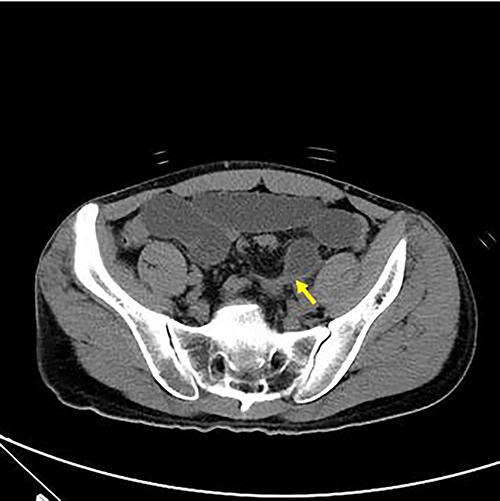

Axial view of abdominal CT revealing intersigmoid hernia with arrow indicating the leading point.

With no indications for immediate surgical intervention, the initial treatment plan for the patient was decided for conservative management with non per os (NPO) and Levin tube drainage. The patient, however, complained of aggravated abdominal pain after 12 h of conservative care, with elevated WBC count of 15 590/mm3. Changes were found in the abdominal X-ray showing manifestations of newly appeared step-ladder sign (Fig. 1a and b), and the CT scan displayed aggravated dilation of small bowel with a leading point of the mechanical obstruction in the LLQ area (Fig. 2).